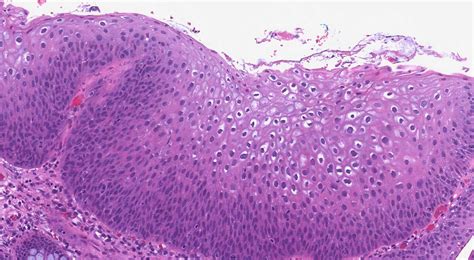

The term Low Grade Squamous Intraepithelial Lesion describes cells that look slightly abnormal under a microscope. These squamous cells line the outer surface of the cervix. When these cells are infected by certain strains of HPV, they may begin to change their shape or size. The “low-grade” designation indicates that the changes are mild and that the cells are not yet showing signs of becoming cancerous. In most cases, the body’s immune system is capable of clearing the HPV infection on its own, allowing the cervix to return to a normal, healthy state without the need for invasive medical procedures.

Medical professionals typically identify LSIL during routine cervical cancer screening procedures, such as a Pap test or a co-test that includes HPV testing. When a pathologist examines the cells collected during these tests, they look for specific cellular characteristics that indicate the presence of a lesion.